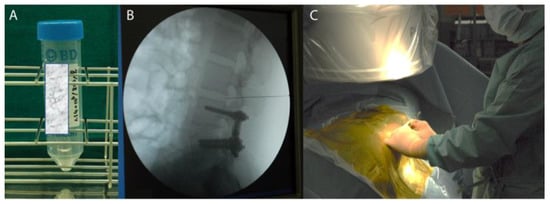

6. Our Experience